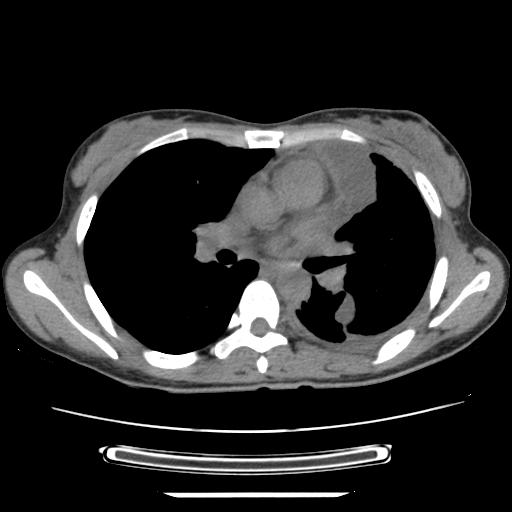

女,29岁,胸部不适,在外院胸片提示胸腔积液,到我院ct检查。

纵膈窗

1、左侧包裹性积液伴叶间积液 2、右肺多发结节考虑增殖结节

左侧纵隔胸膜包裹性积液、左侧胸腔积液、胸膜肥厚粘莲,考虑结核性胸膜炎

左肺上叶不张,左侧胸水,叶间裂积液,纵隔淋巴结,脾脏钙化,考虑左肺上叶支气管内膜结核,结核性胸膜炎,脾结核

考虑:1.两肺tb;2.左侧胸膜炎、胸腔积液。

考虑两肺结核,左侧包裹性积液,叶间积液。

支持两肺继发性肺结核,左侧胸膜腔包裹性积液、胸膜肥厚,脾内多发钙化(结核钙化)。

右肺多发结节。左胸腔多发包裹性积液。